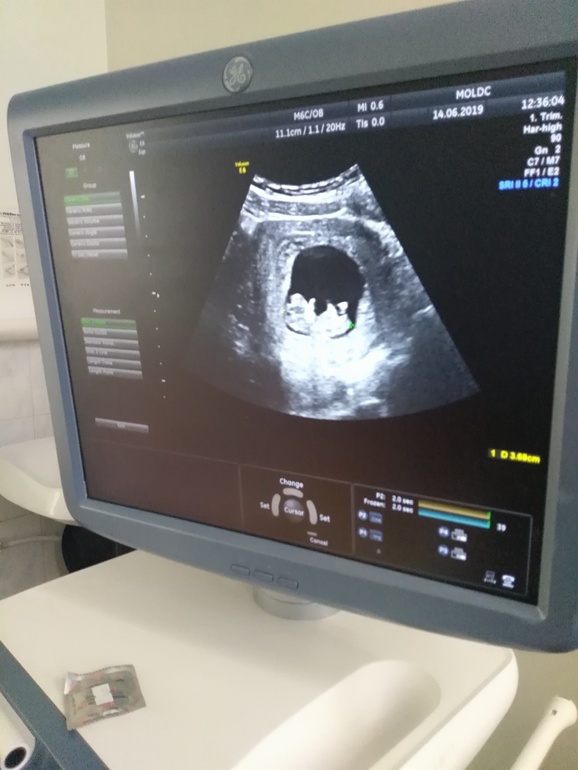

Тоже была зб 2года назад. Потом не получалось. До скрининга была на 5узи,последний раз на 10ой неделе,за эти две недели с ума сходила ,купила доплер пока ничего не услышала. А вчера был скрининг я просто тряслась перед кабинетом. Когда датчик приложили к животу а ребетеныш там шевелится и вроде даже как пальчик во рту держал или у рта. Слезы счастья потекли не произвольно. Врач говорит вам плохо,а я лежу и думаю нет мне очень хорошо. Единственное скрининг длился минуты 3-4. Это нормально думаю или нет? Огорчило то что утолщение матки сзади,видимо из за тонуса. Удачи вам 20го все будет хорошо. 🤰💐

Ждем фото, все будет хорошо. Не переживайте. Нам еще три недели ждать. Уффф